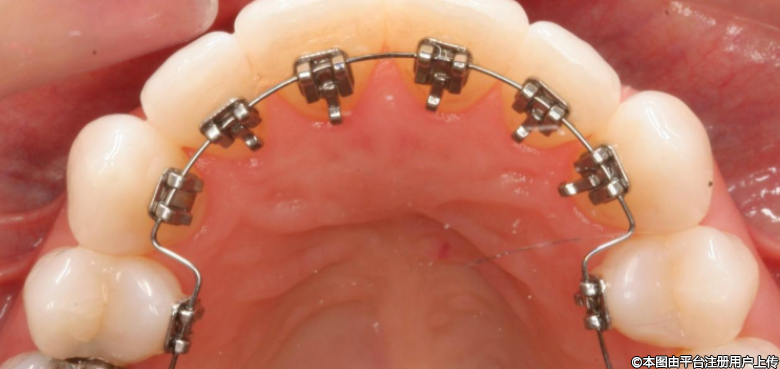

3、舌側矯治器

舌側矯治器將托槽安裝在牙齒舌側面,完全隱蔽不影響外觀,美觀性極佳。適用于演藝人員等特殊職業(yè)需求者。但操作難度大,可能影響發(fā)音和舌體活動,清潔難度較高,治療費用通常較昂貴。